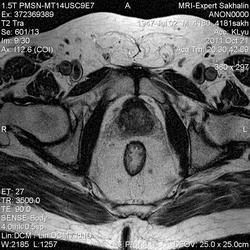

Сегодняшний пациент направлен врачом Онкодиспансера-как обычно без документов, выписок , результатов исследований)))Перенес операцию по удалению опухоли прямой кишки , наложена колостома.

Зато вопросы в направлении:1Протяженность опухоли.2.Depositae in hepar.3Мезоректум.При этом назначил только малый таз....

Прошу помощи!Во-первых, не совсем понятная простата и мочевой пузырь; на некоторых сканах есть признаки тесного прилежания простаты к стенке кишки.В общем-я ничего не понимаю-что удалили!

Признаков распространения опухоли в мезоректум я не вижу (наружный контур кишки четкий, ровный), простата и апоневроз Денонвилье интактны. А в мочевом скорее всего утолщенная межмочеточниковая складка попала в срез .Элевация простаты в мочевой пузырь? Нужны короналы с мочевым пузырем и ПЖ.

Ольга Сергеевна, я завтра у направляющего врача узнаю.Простата гиперплазирована, но прорастания достоверно не вижу.Мезоректум, кажется, тоже интактен.Спасибо за комментарий!